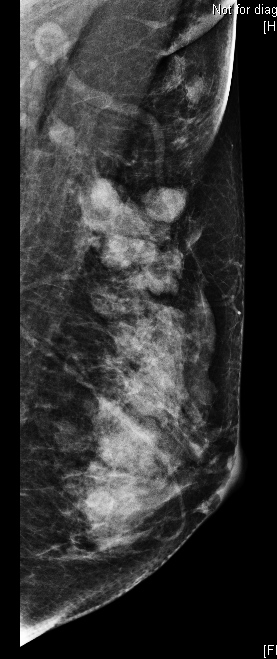

36 year old female comes with history of left breast lump. She is evaluated outside for same and HPR is papillary lesion. She comes to our hospital, we repeat her mammogram and USG, which is suggestive of a high density large mass with lobular margin in upper outer quadrant of left breast. As out side HPR is discordant with imaging finding, we repeat her biopsy and MRI. Repeat biopsy is suggestive of again papillary lesion. And MRI is suggestive of invasion of chest wall muscle. What do we do now?

Adenomyoepithelioma is a primary breast neoplasm of rare entity caused by proliferation of both epithelial and myoepithelial components, Benign to low grade malignant behavior and has a propensity for recurrence. Either epithelial or myoepithelial component can show malignant transformation so thorough evaluation recommended*. Overlap of histopathological features usually lead to misinterpretation as invasive carcinoma or intraductal papilloma or sclerosing adenosis. Complete wide excision with negative margins is standard treatment to prevent local recurrence. It is difficult to diagnose this on imaging alone, however familiarity with this rare entity to radiologist is essential to raise possibility.

Final histopathology was suggestive of Adenomyoepithelioma (AME). (Few foci of atypia were seen, however there was no malignancy)